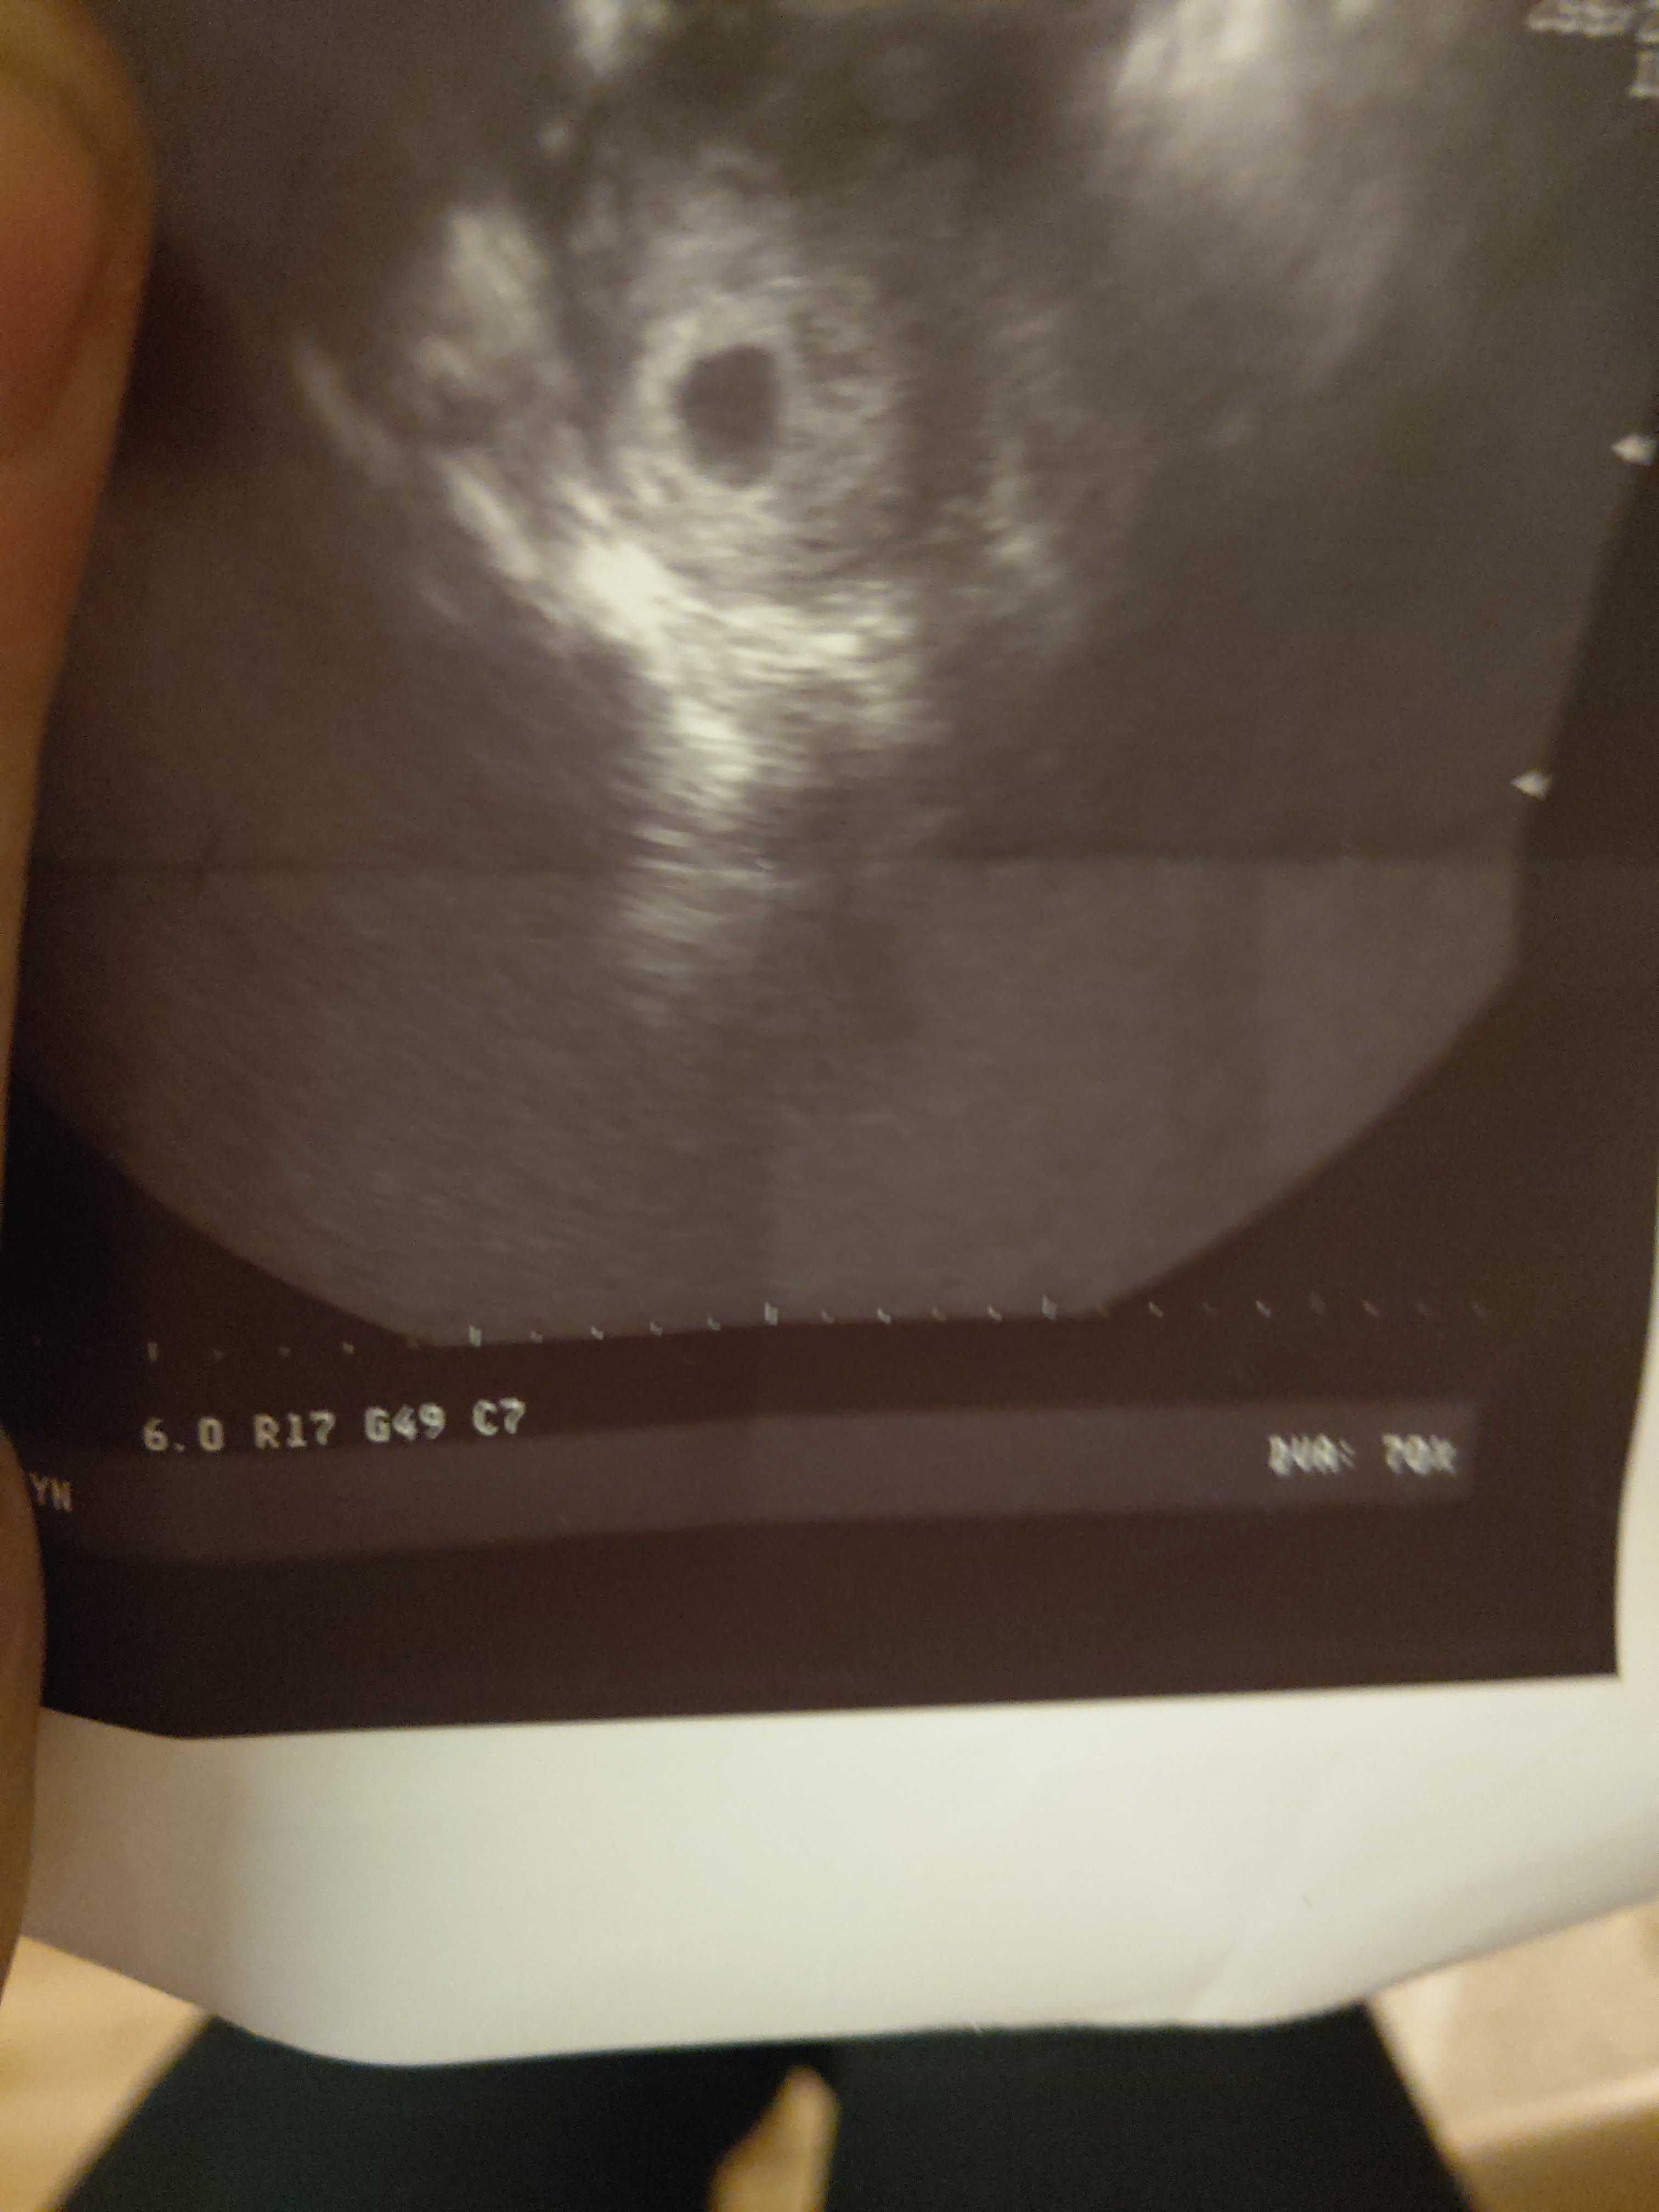

Byłam, pochwalił że wzięłam luteine, ogólnie jeszcze nic nie widac ale coś się tam dzieje;) stwierdził że to 5/6 tydz;) kolejna wizyta za tydz w czwartek wtedy biorę l4 mam w pracy bardzo nie przyjemna osobę która jest mi nieprzychylna i szkoda mi jednak nerwów.. IMAG1211.jpg